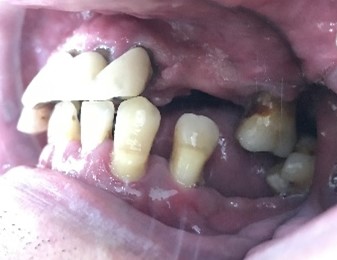

Before

赤丸は抜歯しました

After

【義歯を装着したところ】

【義歯を外したところ】